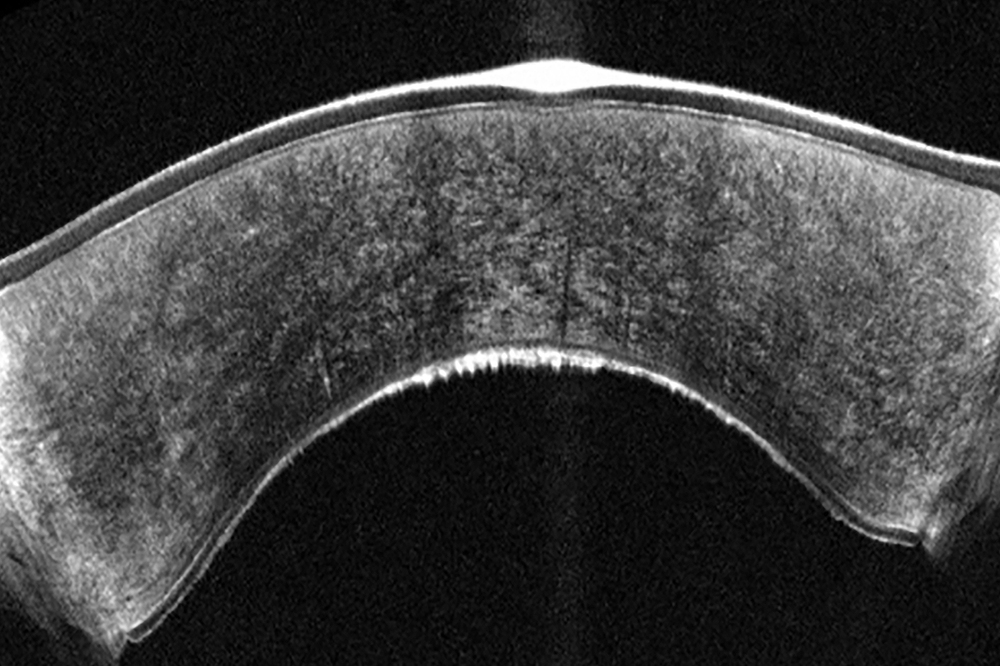

Hoge-resolutie OCT-technologie maakt gedetailleerde visualisatie van de corneale structuren mogelijk, inclusief nauwkeurige meting van de epitheliale dikte. Deze meting is cruciaal voor de vroege detectie van corneale ectasie. Epitheliale diktemapping ondersteunt bovendien de chirurgische planning, wat bijdraagt aan optimale resultaten van refractiechirurgie. OCT-beeldvorming is bovendien essentieel voor:

- postoperatieve zorg;

- het volgen van genezing;

- en het opsporen van complicaties na LASIK of keratoplastiek.

Door Scheimpflug-technologie en OCT te combineren ontstaat een volledig beeld: Scheimpflug toont lichtverstrooiende structuren in het voorste oogsegment met blauw licht, terwijl OCT ongeëvenaarde details geeft. Beide metingen worden gelijktijdig uitgevoerd op exact dezelfde locaties, wat directe en gedetailleerde visualisatie van alle afwijkingen mogelijk maakt.

- OCT geeft gedetailleerde structuren